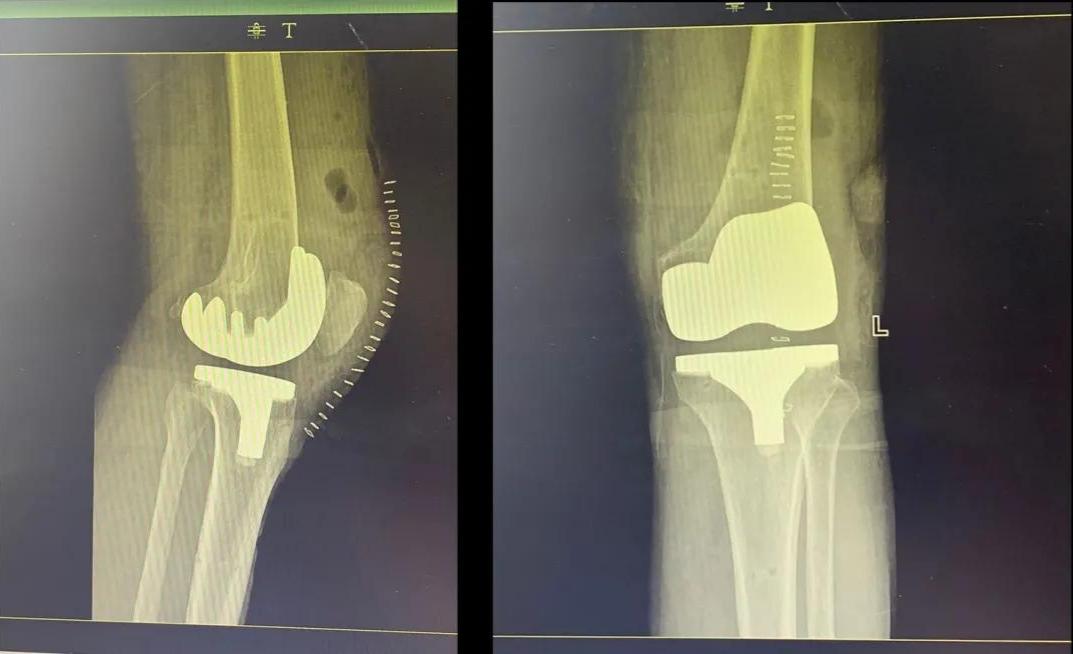

(一些术后图)

开展关节置换、关节翻修术和关节镜手术;能熟练地开展髋关节、膝关节和肩关节置换术;关节镜下的关节清理、半月板切除、半月板成形、半月板缝合、髁间窝成形、前后交叉韧带重建等手术,尤其开展了各类保膝手术,如单髁置换术、截骨矫形手术。同时开展了人工智能计算机导航辅助关节置换手术。